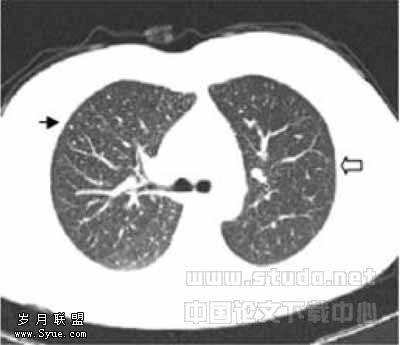

结节的大小、CT扫描参数、图像噪音等影响CT发现肺结节的因素中,以结节大小最重要[11]。Schweden等[12]的研究表明:单排螺旋CT的LD (30mA)与SD (200mA)扫描发现肺结节具有较好的一致性,分歧多数发生在邻近血管的肺结节。Diederich等[13]指出单排螺旋CT的SD与LD扫描发现直径≤5mm、6~10mm、>10mm肺结节的数量无统计学差异;如果LDCT放射剂量太低(25mA,螺距2),图像可能出现伪影,干扰≤5mm肺结节的观察。本文LD与SD扫描发现肺结节均具有较好的一致性,差异主要发生在<5mm的小结节:部分SDCT可见的肯定或模糊的小结节,LDCT显示模糊或未见到(图3,4);部分LDCT显示肯定或模糊的小结节,在SDCT显示模糊或未见到(图5,6);LDCT显示粟粒结节或密度较淡的小结节不如SDCT。另外本文中组的Kappa值略低于B组,但LD1扫描的实际emAs均值却略高于LD2,这与随着emAs降低,图像噪声将增加,影响发现肺小病变的理论不符。我们重新查阅原始资料,发现A组直径<5mm肺结节中粟粒结节和密度较淡的小结节明显多于B组,这可能是造成A组Kappa值略低于B组的原因。Karabulut等[11]研究指出SDCT与LDCT在发现肺结节数量上无显著差异,LDCT发现<5mm肺结节的敏感性为88.1%,发现≥5mm肺结节的敏感性为97.4%,发现肺结节的总敏感性为92.5%。本文结果与报道相符,本文将“模糊”肺结节也算入后,LD扫描发现肺结节敏感性、准确度较只“肯定”肺结节的升高,但特异性明显降低,可见LDCT扫描时注意对“模糊”的肺结节的诊断观察,会导致误诊增加,却能有效减少漏诊肺结节。

图1,2分别为同一层面的常规剂量与低剂量CT,可见少量伪影,不影响观察肺结节图3,4分别为同一层面的常规剂量与低剂量CT图像,示未见伪影图3示小于5mm肯定肺结节(→?)和模糊肺结节(←?),图4分别显示为肯定(→?)、未见(←?)